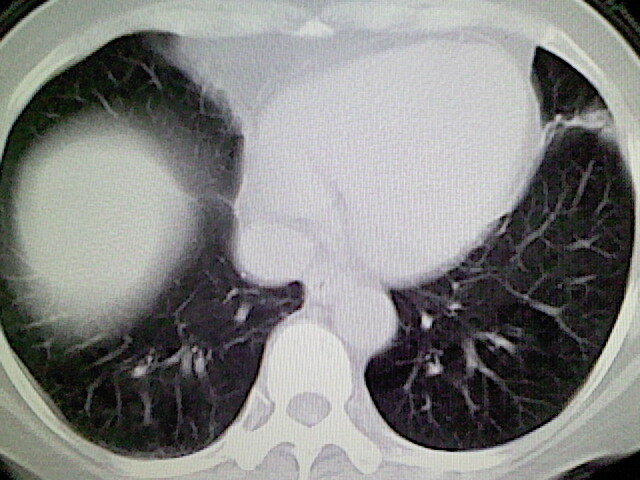

女,52岁,咳嗽,咳痰多日

左下肺陈旧纤维索条!

左肺舌段炎性改变

我见过几例,为炎症后纤维条索

慢性炎症后改变

考虑慢性炎性病灶粘连牵拉改变。

左肺舌叶纤维锁条病变。

左肺上叶下舌段炎症并局部胸膜反应。

左肺舌叶纤维索条影。

左肺舌叶段陈旧性病变

左肺舌段炎性反应。片子的质量太不好了。

左肺舌段炎性

炎性改变

左肺舌叶纤维索条影